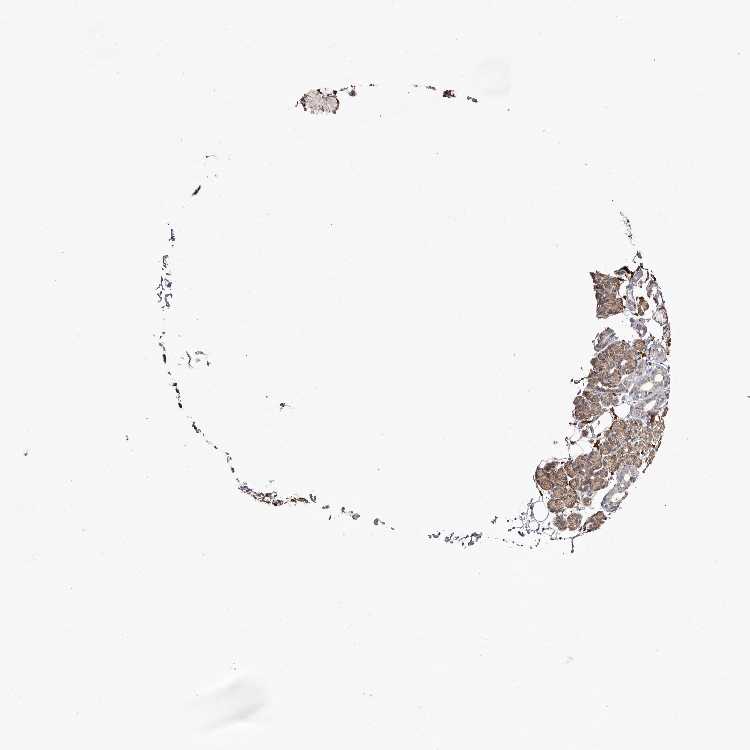

SALIVARY GLAND - Antibody stainingi

Antibody staining in the annotated cell types in the current human tissue is reported as not detected, low, medium, or high, based on conventional immunohistochemistry profiling in selected tissues. This score is based on the combination of the staining intensity and fraction of stained cells.

Each image is clickable and will lead to virtual microscopy that enables deeper exploration of all samples and also displays staining intensity scores, fraction scores and subcellular localization as well as patient and tissue information for each sample.

Antibody HPA028179

Glandular cells Medium